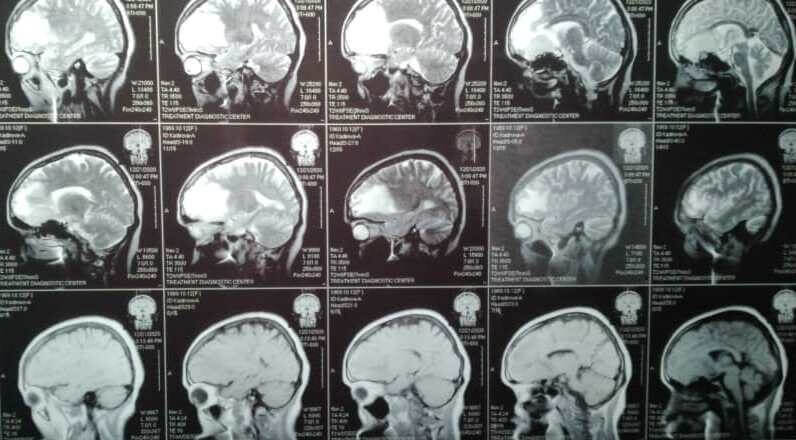

С 15 по 16 января 2021 года проректор КГМА им.И.К.Ахунбаева, профессор-нейрохирург Кенешбек Ырысов по линии санитарной авиации провел сложнейшие операции трем пациентам с гигантскими опухолями головного мозга в отделении нейрохирургии Ошской межобластной объединенной клинической больницы. Операция прошла успешно, пациенты пришли в себя без неврологического дефицита и каких-либо других осложнений.